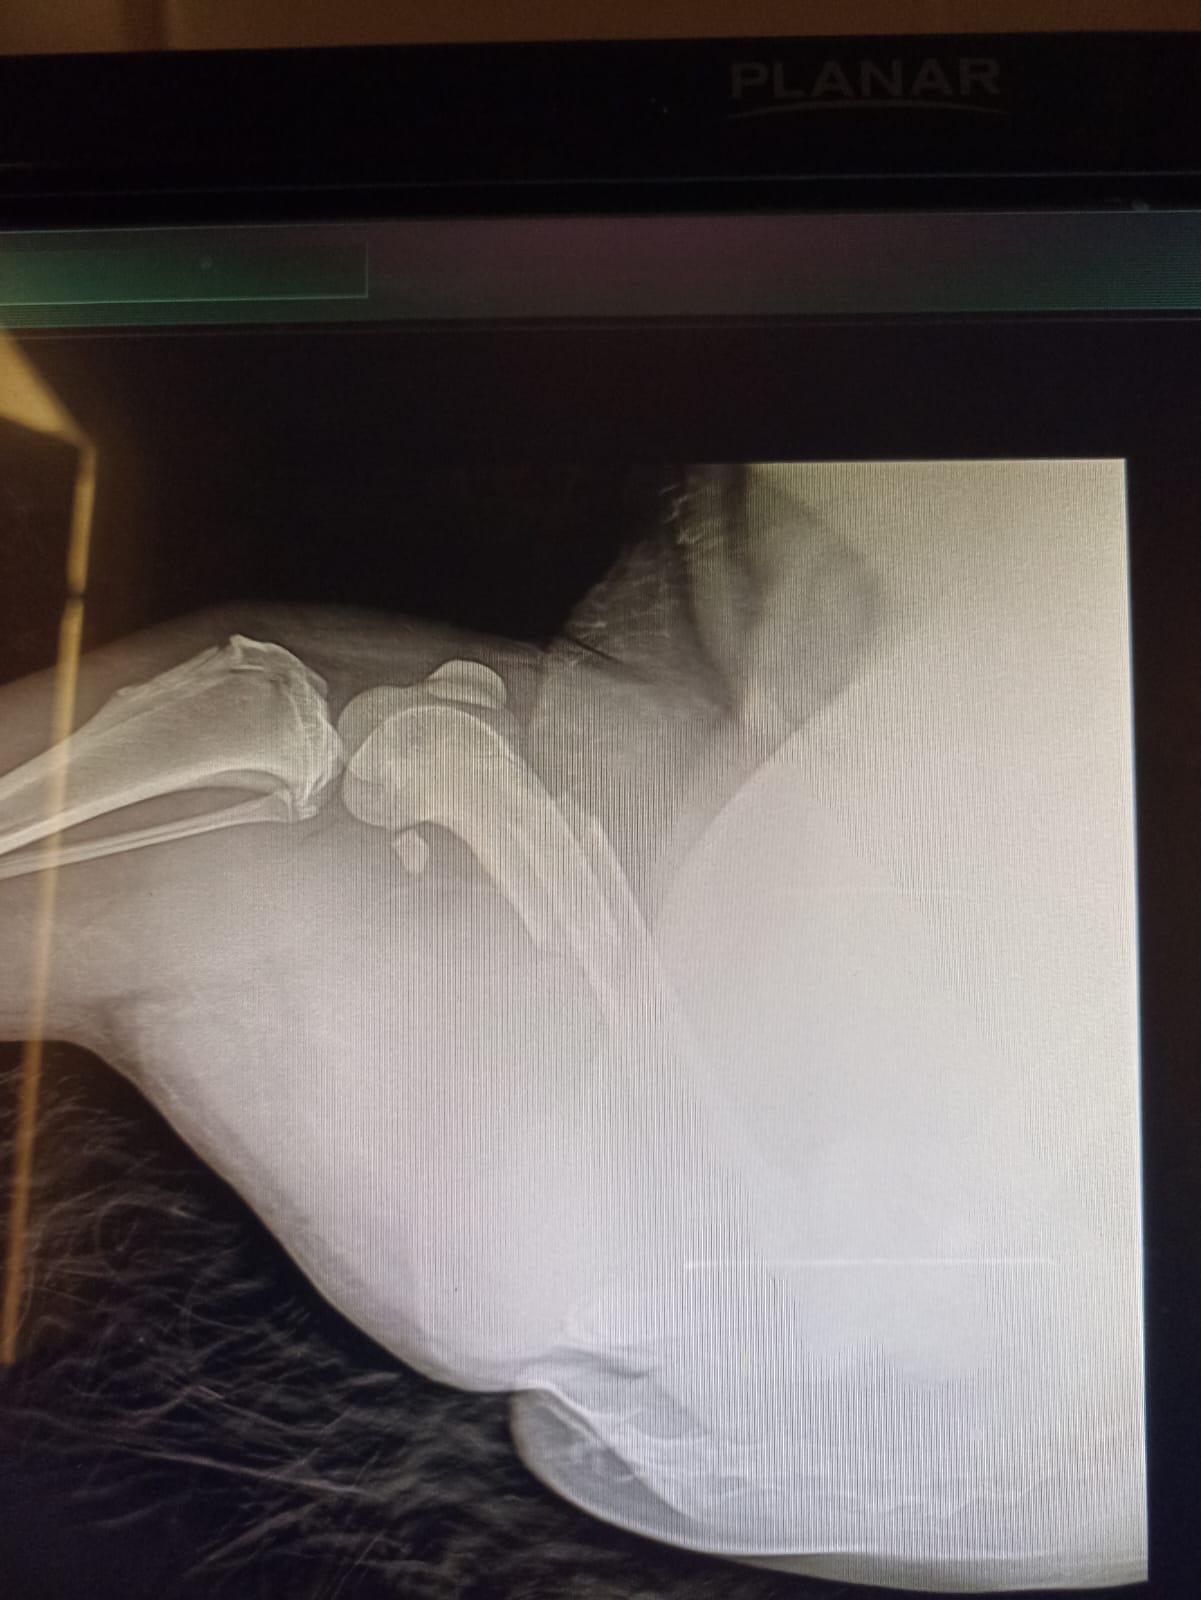

Волонтёр привела молодую суку ризена со сломанной лапой в клинику к Насте pani Stasi. Вроде перелом не сильно свежий.

Ногу будет хирург смотреть и может в ближайшее время прооперируют.

Собаке 8 месяцев, хозяйка попала в реанимацию.

Её забрала заводчица. И что-то там у них случилось, то ли лошадь понесла, то ли что, в общем, собака перепрыгивала через телегу и сломала лапу. У заводчицы тоже ключица сломана, может ещё что-то.

Ветеринар позвонила знакомому волонтёру, говорит, чего усыплять, я её соберу, рентген только надо.

Операцию сделали, собрали лапу на две пластины. Выписка попозже будет.

Да, задняя правая сломана.